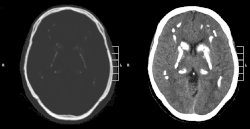

CT scan of characteristic calcifications of the disease

Primary familial brain calcification[1] (PFBC), also known as familial idiopathic basal ganglia calcification (FIBGC) and Fahr's disease,[1] is a rare,[2] genetically dominant or recessive, inherited neurological disorder characterized by abnormal deposits of calcium in areas of the brain that control movement. Through the use of CT scans, calcifications are seen primarily in the basal ganglia and in other areas such as the cerebral cortex.[3]

Brain CT scan is the preferred method of localizing and assessing the extent of cerebral calcifications.